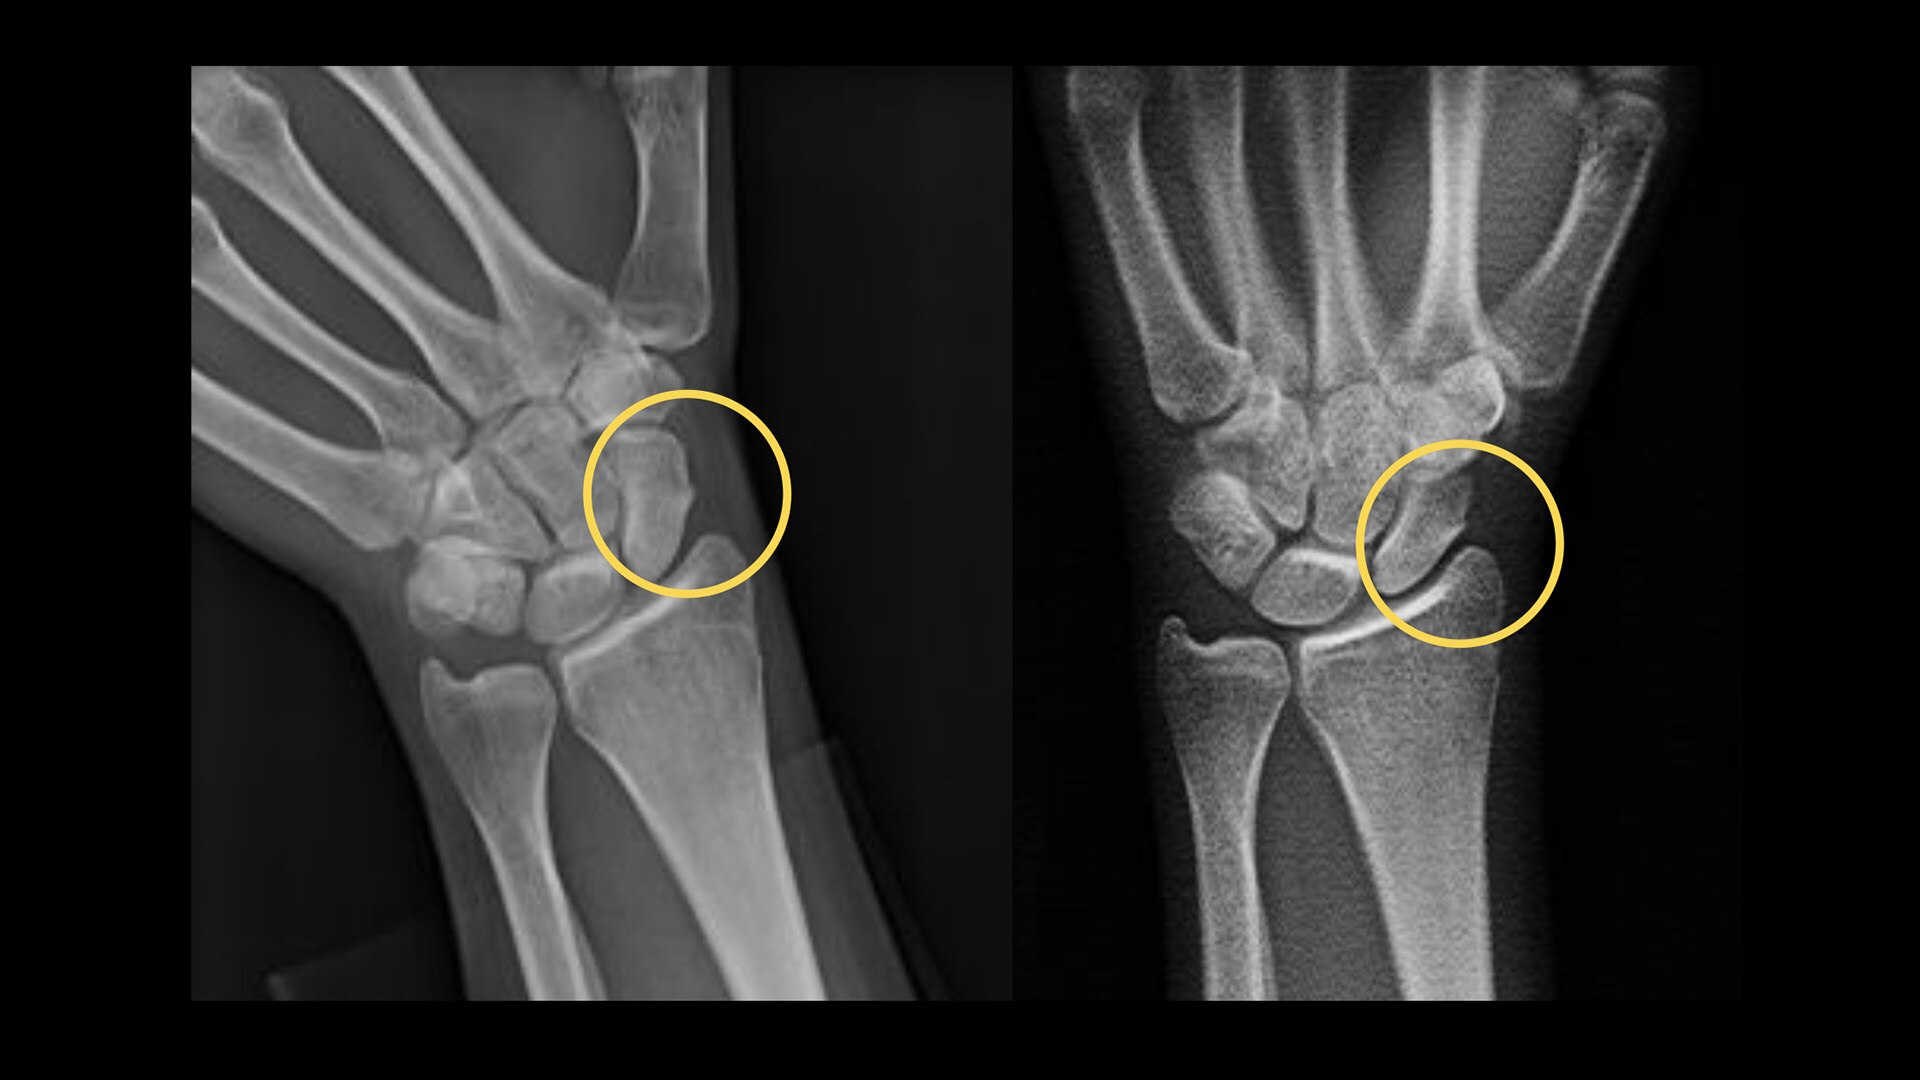

Orthopedics